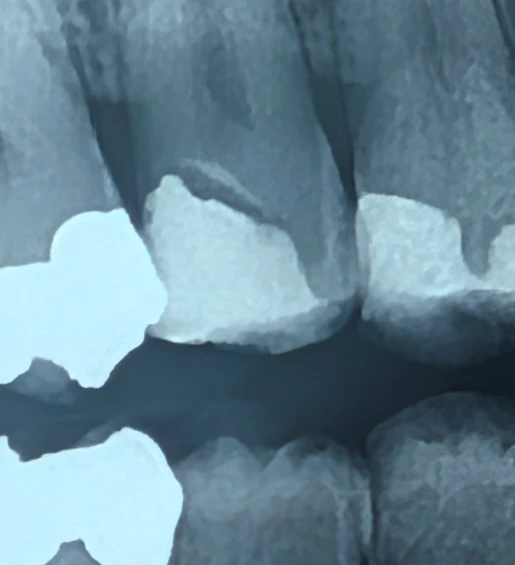

رادیولوسنسی منظم زیر ترمیم و تمایز آن از پوسیدگی ثانویه

در رادیوگرافی‌های بایت‌وینگ، مشاهدهٔ رادیولوسنسی در مجاورت ترمیم‌ها می‌تواند بلافاصله ذهن را به سمت پوسیدگی ثانویه هدایت کند.

با این حال، در برخی موارد ناحیه‌ای رادیولوسنت با مرزهای مشخص در زیر ترمیم دیده می‌شود که منشأ آن پوسیدگی نیست، بلکه به مواد ترمیمی مربوط است.

وقتی رادیولوسنسی:

دارای مرزهای صاف و منظم است

ضخامتی یکنواخت دارد

موازی با کف حفره دیده می‌شود

و به‌صورت محدود در زیر ترمیم باقی می‌ماند

احتمال پوسیدگی ثانویه کاهش یافته و تفسیر به سمت وجود لاینر یا کامپوزیت‌های رادیولوسنت هدایت می‌شود.

در پوسیدگی دنتینی انتظار داریم:

حاشیه‌های نامنظم و diffuse

گسترش تدریجی به طرفین

کاهش تدریجی دانسیته

و الگوی انتشار بیولوژیک در امتداد دنتین

در حالی‌که الگوی یکنواخت و مهندسی‌شده، رفتار بیولوژیک پوسیدگی را تقلید نمی‌کند.